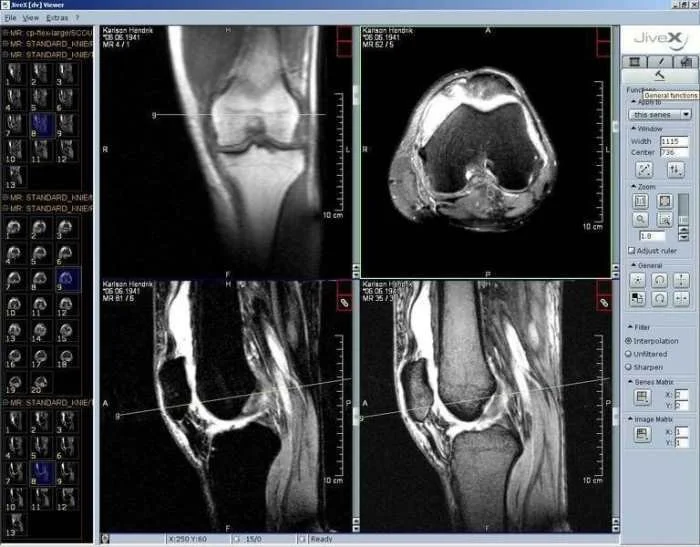

Популярные программы для просмотра DICOM-файлов (Windows, macOS, iOS, Android и Linux)

Видео-обзор лучших программ для просмотра DICOM-файлов